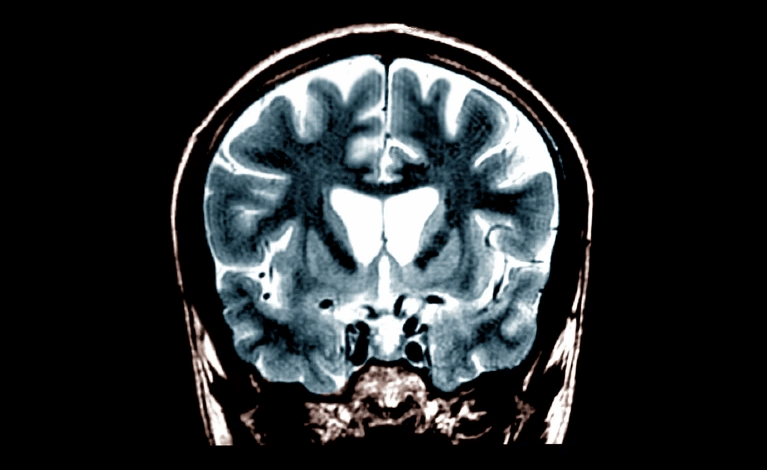

A administração do tratamento requer uma cirurgia demorada, na qual os médicos utilizam imagens de ressonância magnética para inserir com precisão uma cânula através de pequenos orifícios no crânio. A terapia é então infundida lentamente no estriado, uma parte do cérebro que está entre as primeiras e mais afetadas pela doença de Huntington.